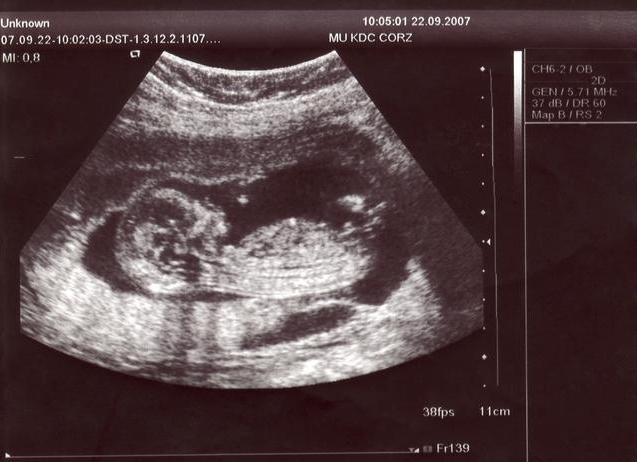

四維彩超是一種先進(jìn)的醫(yī)學(xué)成像技術(shù),能夠在孕期實(shí)時(shí)觀察胎兒的發(fā)育情況,與傳統(tǒng)的二維、三維彩超相比,四維彩超能夠提供更清晰、更立體的圖像,讓準(zhǔn)父母更直觀地了解胎兒的成長過程。

2、觀察圖像:在四維彩超圖像上,男性胎兒的生殖器官呈現(xiàn)為細(xì)小的小雞冠狀結(jié)構(gòu),而女性胎兒的生殖器官則呈現(xiàn)為較為平滑的橢圓形結(jié)構(gòu),通過觀察這些特征,可以初步判斷胎兒的性別。

圖解展示

(此處可插入一系列四維彩超圖像,展示男性胎兒和女性胎兒生殖器官的不同特征)